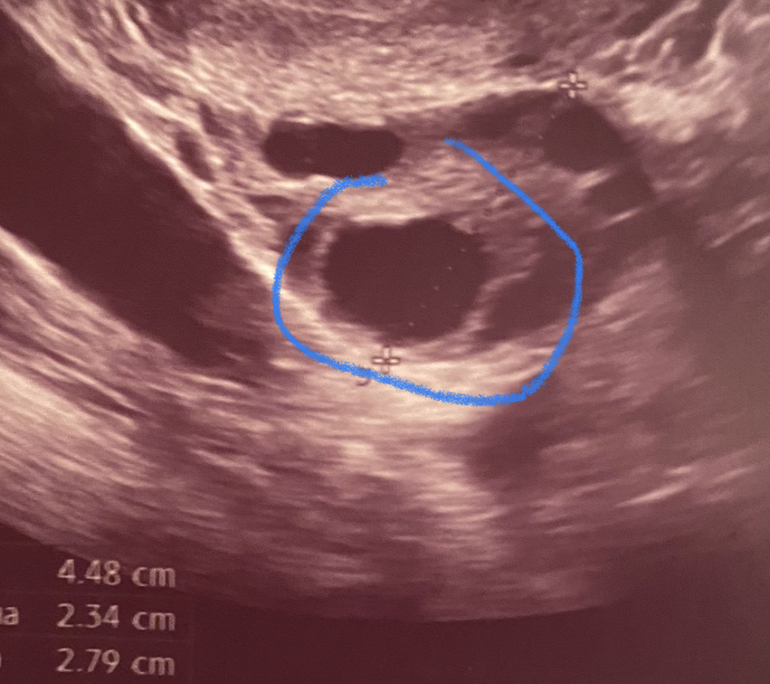

Фото ДФ 21 на 11 Дц

То что фоллик сдулся, сказала узистка, просто мой врач работает в первой пловине дня, я не смогла к ней попасть. А сегодня я ей рассказала, она сказала что меньше рамер (14 мм), потому что Жт образоваться не успело, что позже оно будет больше. Я видимо не правильно написала здесь. Только вот верхнее фото - это типа должн быть ЖТ. А нижнее фото-это какой он был прям перед уколом..

У меня закрались сомнения. Вы говорите про ЖТ, о верхнем фото или о нижнем?

На нижнем фоллик 21 мм, а сверху как раз что то непонятное. Вы о верхней фотке???

О верхней. На нижней ваш квадратный фоллик)